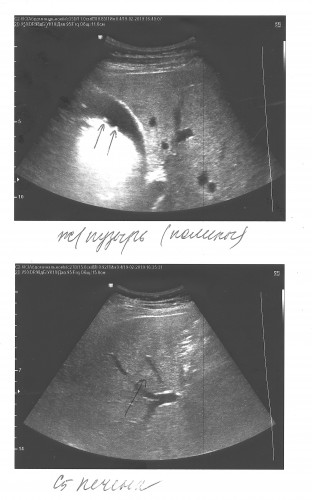

4) консультация врачей требуются ли дальнейшие обследования на счет гемангиомы печени - КТ или МРТ